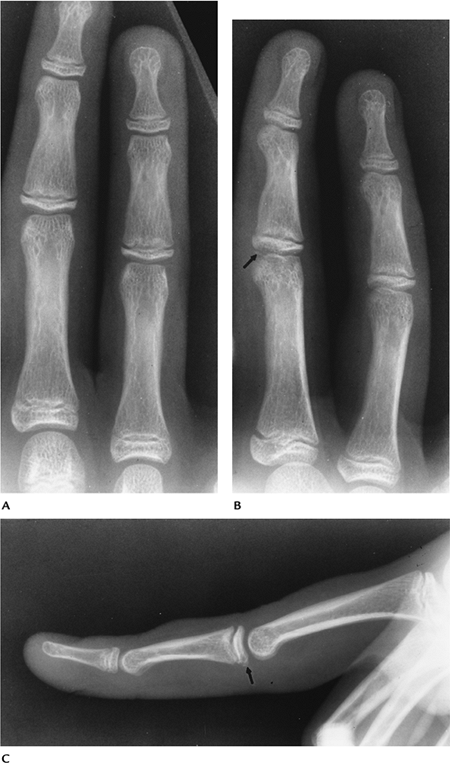

Fractures/Dislocations: Phalangeal Fractures/Dislocations

Key Facts

-

Phalangeal fractures are the most common fractures in the hand. Fractures of the proximal phalanx are most common.

Dislocations of the phalangeal and metacarpophalangeal (MCP) joints usually are dorsal.

Mechanism of injury: direct blows, falls, athletic injuries.

Imaging with PA and lateral radiographs usually is adequate. CT may be required after reduction for osteochondral evaluation.

Treatment: closed reduction unless there is shortening, angulation, or significant articular involvement.

Complications: shortening, rotation, arthrosis, decreased joint function.

![]() |

|

FIGURE 9-26 Lateral radiograph of an angulated proximal phalangeal fracture.

FIGURE 9-27 Lateral view of a dorsal phalangeal dislocation (arrow).

FIGURE 9-29 Lateral view of a hyperflexion Mallet fracture of the distal phalanx.